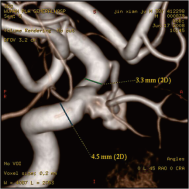

颈内动脉创伤性假性动脉瘤覆膜支架治疗前后(三维像是术前) 右侧颈内动脉后交通动脉瘤栓塞术后完全闭塞